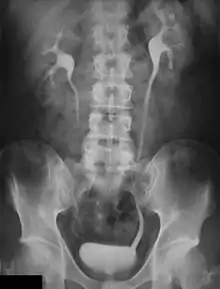

Uma imagem radiológica do sistema urinário.